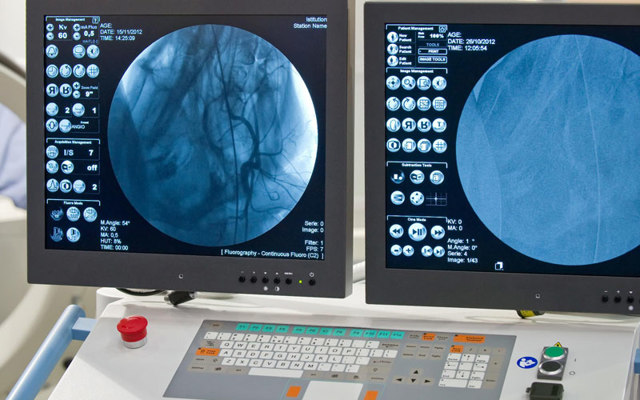

На традиционных рентгенограммах специалист не имеет возможности визуализировать артерии, венозную сеть, лимфатическую сосудистую систему и капилляры, т. к. эти элементы не способны поглощать рентгеновские лучи, аналогично мягким тканям в их окружении.

- Поэтому для диагностики этих анатомических структур производится ангиография сосудов, сопровождающаяся вводом контрастного средства.

- Таким способом осуществляется диагностирование коронарных сосудов сердца или коронарография, исследуется сосудистая сеть головного мозга, шеи и прочие сосуды человеческого организма.

- Под традиционной ангиографией сосудов головного мозга подразумевают рентген головы после контрастирования сосудистой сетки мозга с применением контрастных средств.

- Процедура осуществляется методом пункции или катетеризации экстракраниальных и интракраниальных сосудов, внедрением лекарства и последующего вывода фотографий.

- классическая ангиография — осуществление рентгенограмм с предварительным введением контраста в сосуды головы;

- КТ-ангиография — сканирование системы сосудов в головном мозге рентгенологическим методом с предварительным контрастированием и дальнейшим 3D-моделированием отображения системы кровоснабжения;